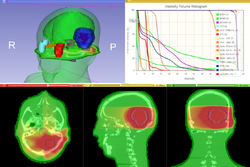

SlicerRT

Qualitative and quantitative comparison of two RT dose distributions

Dose accumulation for adaptive radiation therapy

- Tutorial presentation: pptx pdf

- Dataset: download from MIDAS

- Authors: Csaba Pinter, Andras Lasso, Queen's